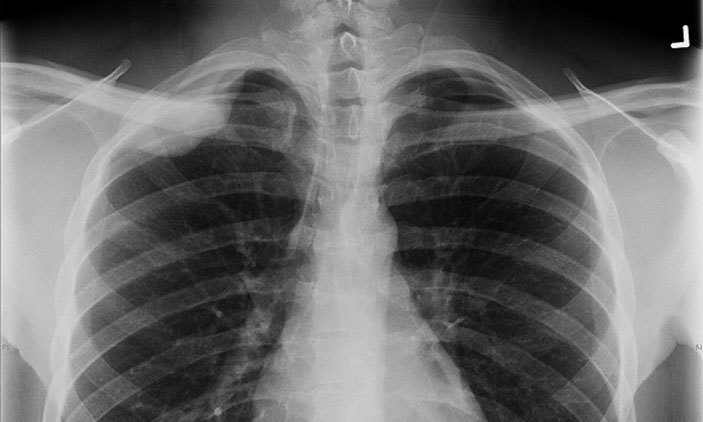

एक्सरे गर्न जाजरकोट आउने दिनको अन्त्य

जाजरकोट । वर्षौदेखि एक्सरे गर्नका लागि डोल्पाको सदरमुकाम दुनै वा जाजरकोट सदरमुकाम आउनुपर्ने मुड्केचुलावासीको दुःख अन्त्य भएको छ । गाउँपालिकाको आफ्नै लगानीमा एक्सरे र ल्याव सेवा शुरु भएपछि वर्षौदेखिको दुःख हटेका हुन् ।

नौ वडा रहेको मुड्केचुलामा बीचभागमा पर्ने राजिकम्दस्थित स्वास्थ्य संस्थामा स्वास्थ्य सहायक र सिनियर अहेवकै भरमा दिनरात स्वास्थ्य सेवा प्रवाह भएपछि सर्वसाधारण खुशी भएका छन् ।